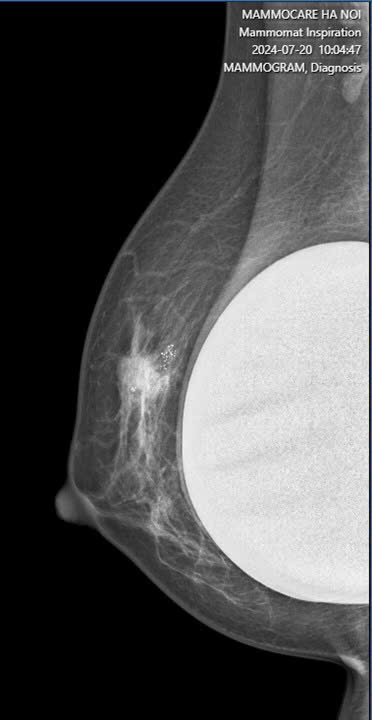

Mới Đặt Túi Ngực Được 6 Tháng, Chị N.T.P Được Chẩn Đoán Ung Thư Vú

Gần đây, Trung tâm Vú Mammocare Hà Nội đã tiếp nhận trường hợp đáng tiếc của chị N.T.P, một bệnh nhân vừa đặt túi ngực được 6 tháng và đến...